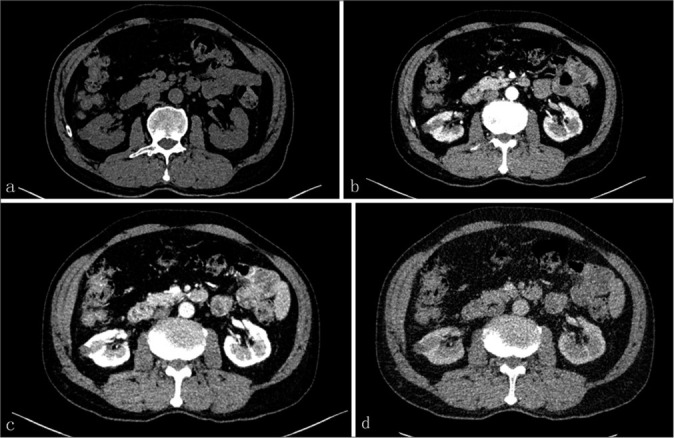

我们报告了一例 71 岁男性肾小管囊性细胞癌(TRCC)患者的病例,这是一种罕见的肾肿瘤。患者因体检时发现右肾中极有一个囊性结节,经泌尿科超声检查后入院。该结节在常规超声检查中呈高回声,在对比增强超声检查中,增厚的囊壁在峰值相的增强强度与肾实质相似。计算机断层扫描血管造影显示肿瘤呈异质性对比增强,磁共振成像显示 T1 加权成像(WI)呈低密度,T2WI 呈高密度。组织学上,海绵表面由典型的管状和多房囊性成分组成,内衬单层上皮细胞。最终病理诊断为 TRCC。患者顺利地接受了腹腔镜右肾根治术。患者出院后随访 12 个月,未发现局部或远处转移迹象。总之,TRCC 应根据放射学和组织学的综合结果进行准确诊断,以确保及时手术和更好的预后。

We present a case involving a 71-year-old male with tubulocystic renal cell carcinoma (TRCC), which is a rare entity of renal neoplasm. The patient was admitted for a cystic nodule on the middle pole of the right kidney by urological ultrasound during physical examination. The nodule presented with hyperechoic on conventional ultrasonic and the enhancing intensity of thicken cystic wall at the peak phase in contrast-enhanced ultrasound was similar to that of the renal parenchyma. Findings from computed tomography angiography exhibited heterogeneously contrast enhancing tumor, and magnetic resonance imaging demonstrated hypointense on T1-weighted images (WI) and hyperintense on T2WI. Histologically, the spongy surface was composed of the typical tubular and multiloculated cystic components lined by a single layer of epithelial cells. The final pathological diagnosis was TRCC. The uneventful laparoscopic right radical nephrectomy was conducted. The patient was followed up for 12 months after discharge and no signs of local or distant metastasis were found. In conclusion, TRCC should be accurately diagnosed on the basis of comprehensive radiological and histological findings to ensure a timely surgery and better prognosis.